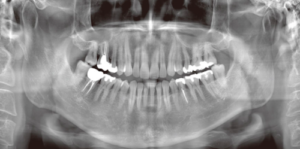

一般的に成人の歯の本数は、親知らずを含めて32本です。

見本の画像は下に2本親知らずがある30本です。

それに対して、この男性は10本多い42本の歯が確認され、

さらに歯ぐきの中に埋まった歯が2本見つかったと報じられています。

- パノラマレントゲン